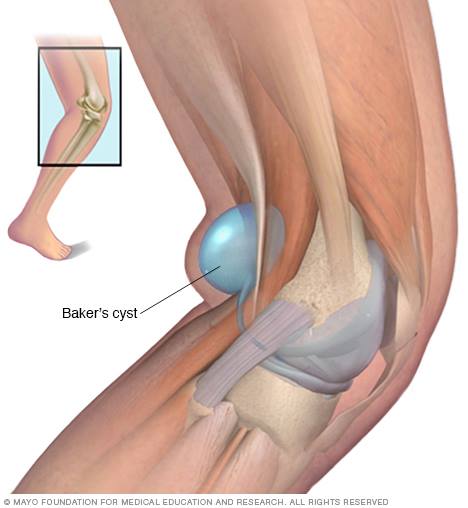

Baker's Cyst of The Knee

A Baker's cyst is a fluid-filled cyst that causes a bulge and a feeling of tightness behind your knee. The pain can get worse when you fully flex or extend your knee or when you're active.

Image courtesy - Mayo Foundation

A Baker's cyst is usually the result of a problem with your knee joint, such as arthritis or a cartilage tear. Both conditions can cause your knee to produce too much fluid, which can lead to a Baker's cyst.